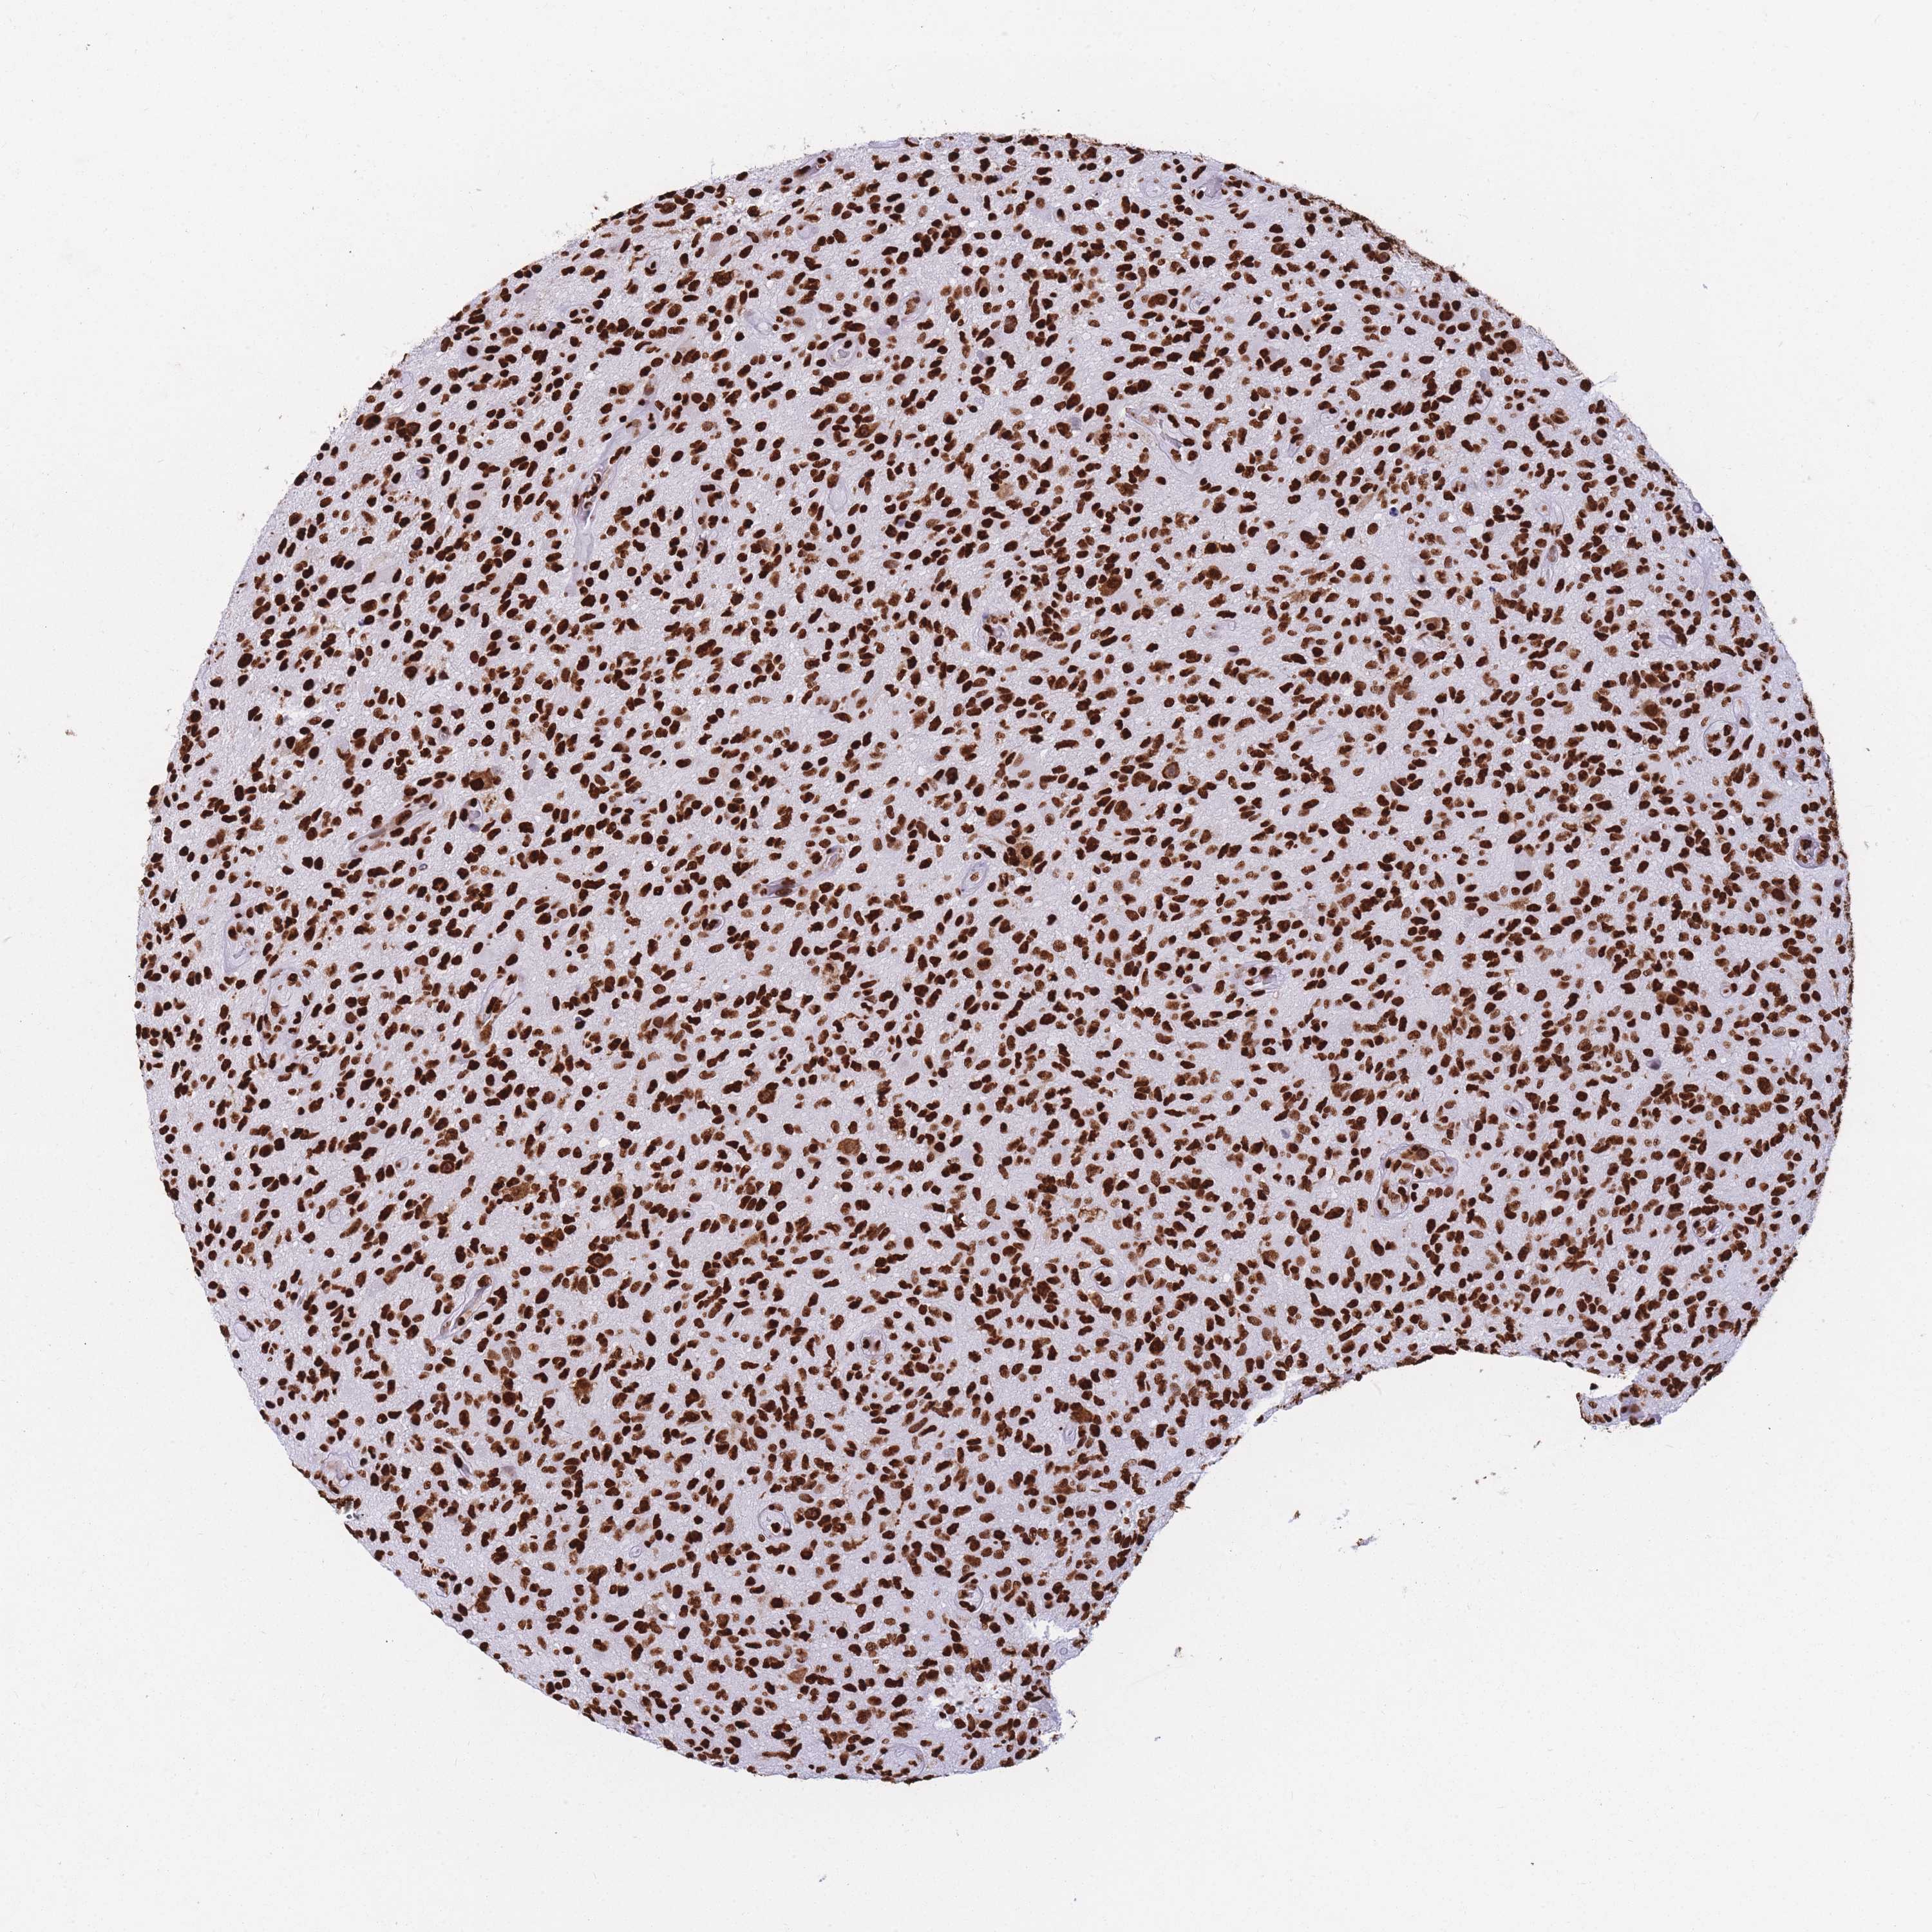

GLIOMA - Protein expressioni

A mouse-over function shows sample information and annotation data. Click on an image to view it in a full screen mode. Samples can be filtered based on level of antibody staining by selecting one or several of the following categories: high, medium, low and not detected. The assay and annotation is described here.

Note that samples used for immunohistochemistry by the Human Protein Atlas do not correspond to samples in the TCGA dataset.

Antibody stainingi

Antibody staining in the annotated cell types in the current human tissue is reported as not detected, low, medium, or high, based on conventional immunohistochemistry profiling in selected tissues. This score is based on the combination of the staining intensity and fraction of stained cells.

Each image is clickable and will lead to virtual microscopy that enables deeper exploration of all samples and also displays staining intensity scores, fraction scores and subcellular localization as well as patient and tissue information for each sample.

Antibody HPA046290

Antibody HPA049475

Antibody CAB046477

Staining

High

Medium

Low

Not detected

Intensity

Strong

Moderate

Weak

Negative

Quantity

>75%

75%-25%

<25%

None

Location

Nuclear

Cytoplasmic/membranous

Cytoplasmic/membranous,nuclear

Glioma, malignant, High grade

Glioma, malignant, Low grade